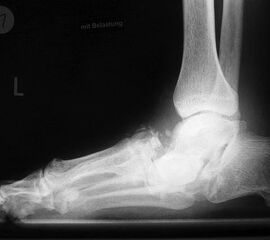

Abbildung 4

DNOAP Typ III (Abb. 4)

Betroffen sind hier das Chopart-Gelenk, also das Talonaviculargelenk und das Calcaneocuboidgekenk. Ein Beteiligung des Naviculocuneiformgelenks ist möglich. Das Längsgewölbe bricht zusammen und es entsteht der klassische diabetische Schaukelfuß – die Kombination aus einer reduzierten Inklination des Kalkaneus in Verbindung mit einer distalen Hackenfußstellung. Nach plantar prominente Knochenkanten und -fragmente können hier ebenfalls zu Ulzerationen der Fußsohle führen.